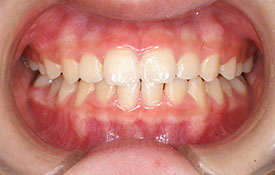

インビザラインの治療例:CASE-2

| プロフィール | 15歳 男性 |

| 所見 | アメリカから転院されて来られた方です。 インビザラインで上下顎の矯正治療を開始し下顎はアメリカで終了しており、上顎のみ治療の後期を担当しました。 アイライナーの装着は、1日平均22時間ほどでした。 |